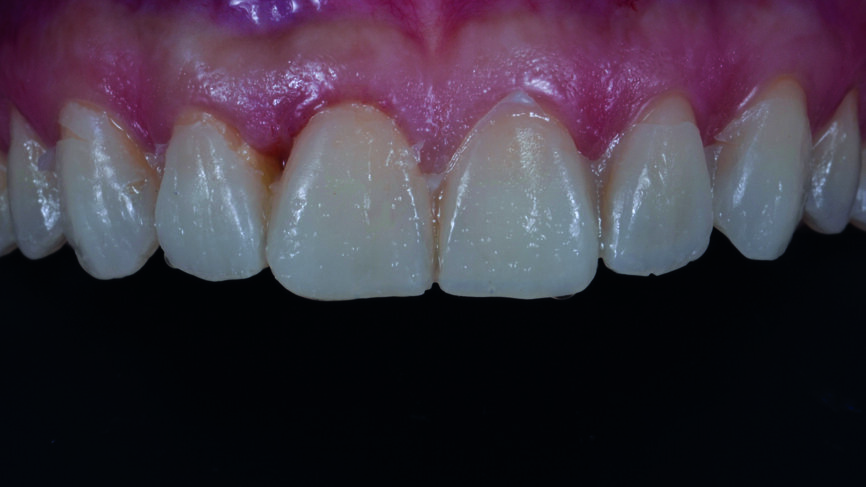

Fig. 2a : Dents antérieures après le traitement orthodontique.

Fig. 2b : Dents antérieures après le traitement orthodontique

Le traitement orthodontique proposé visait à un alignement plus favorable des dents de façon à ne requérir qu‘une préparation minimale pour la pose des facettes et à réduire le recouvrement incisif. Une année après le traitement, la patiente est revenue pour la restauration prothétique définitive (Figs. 2a et b).